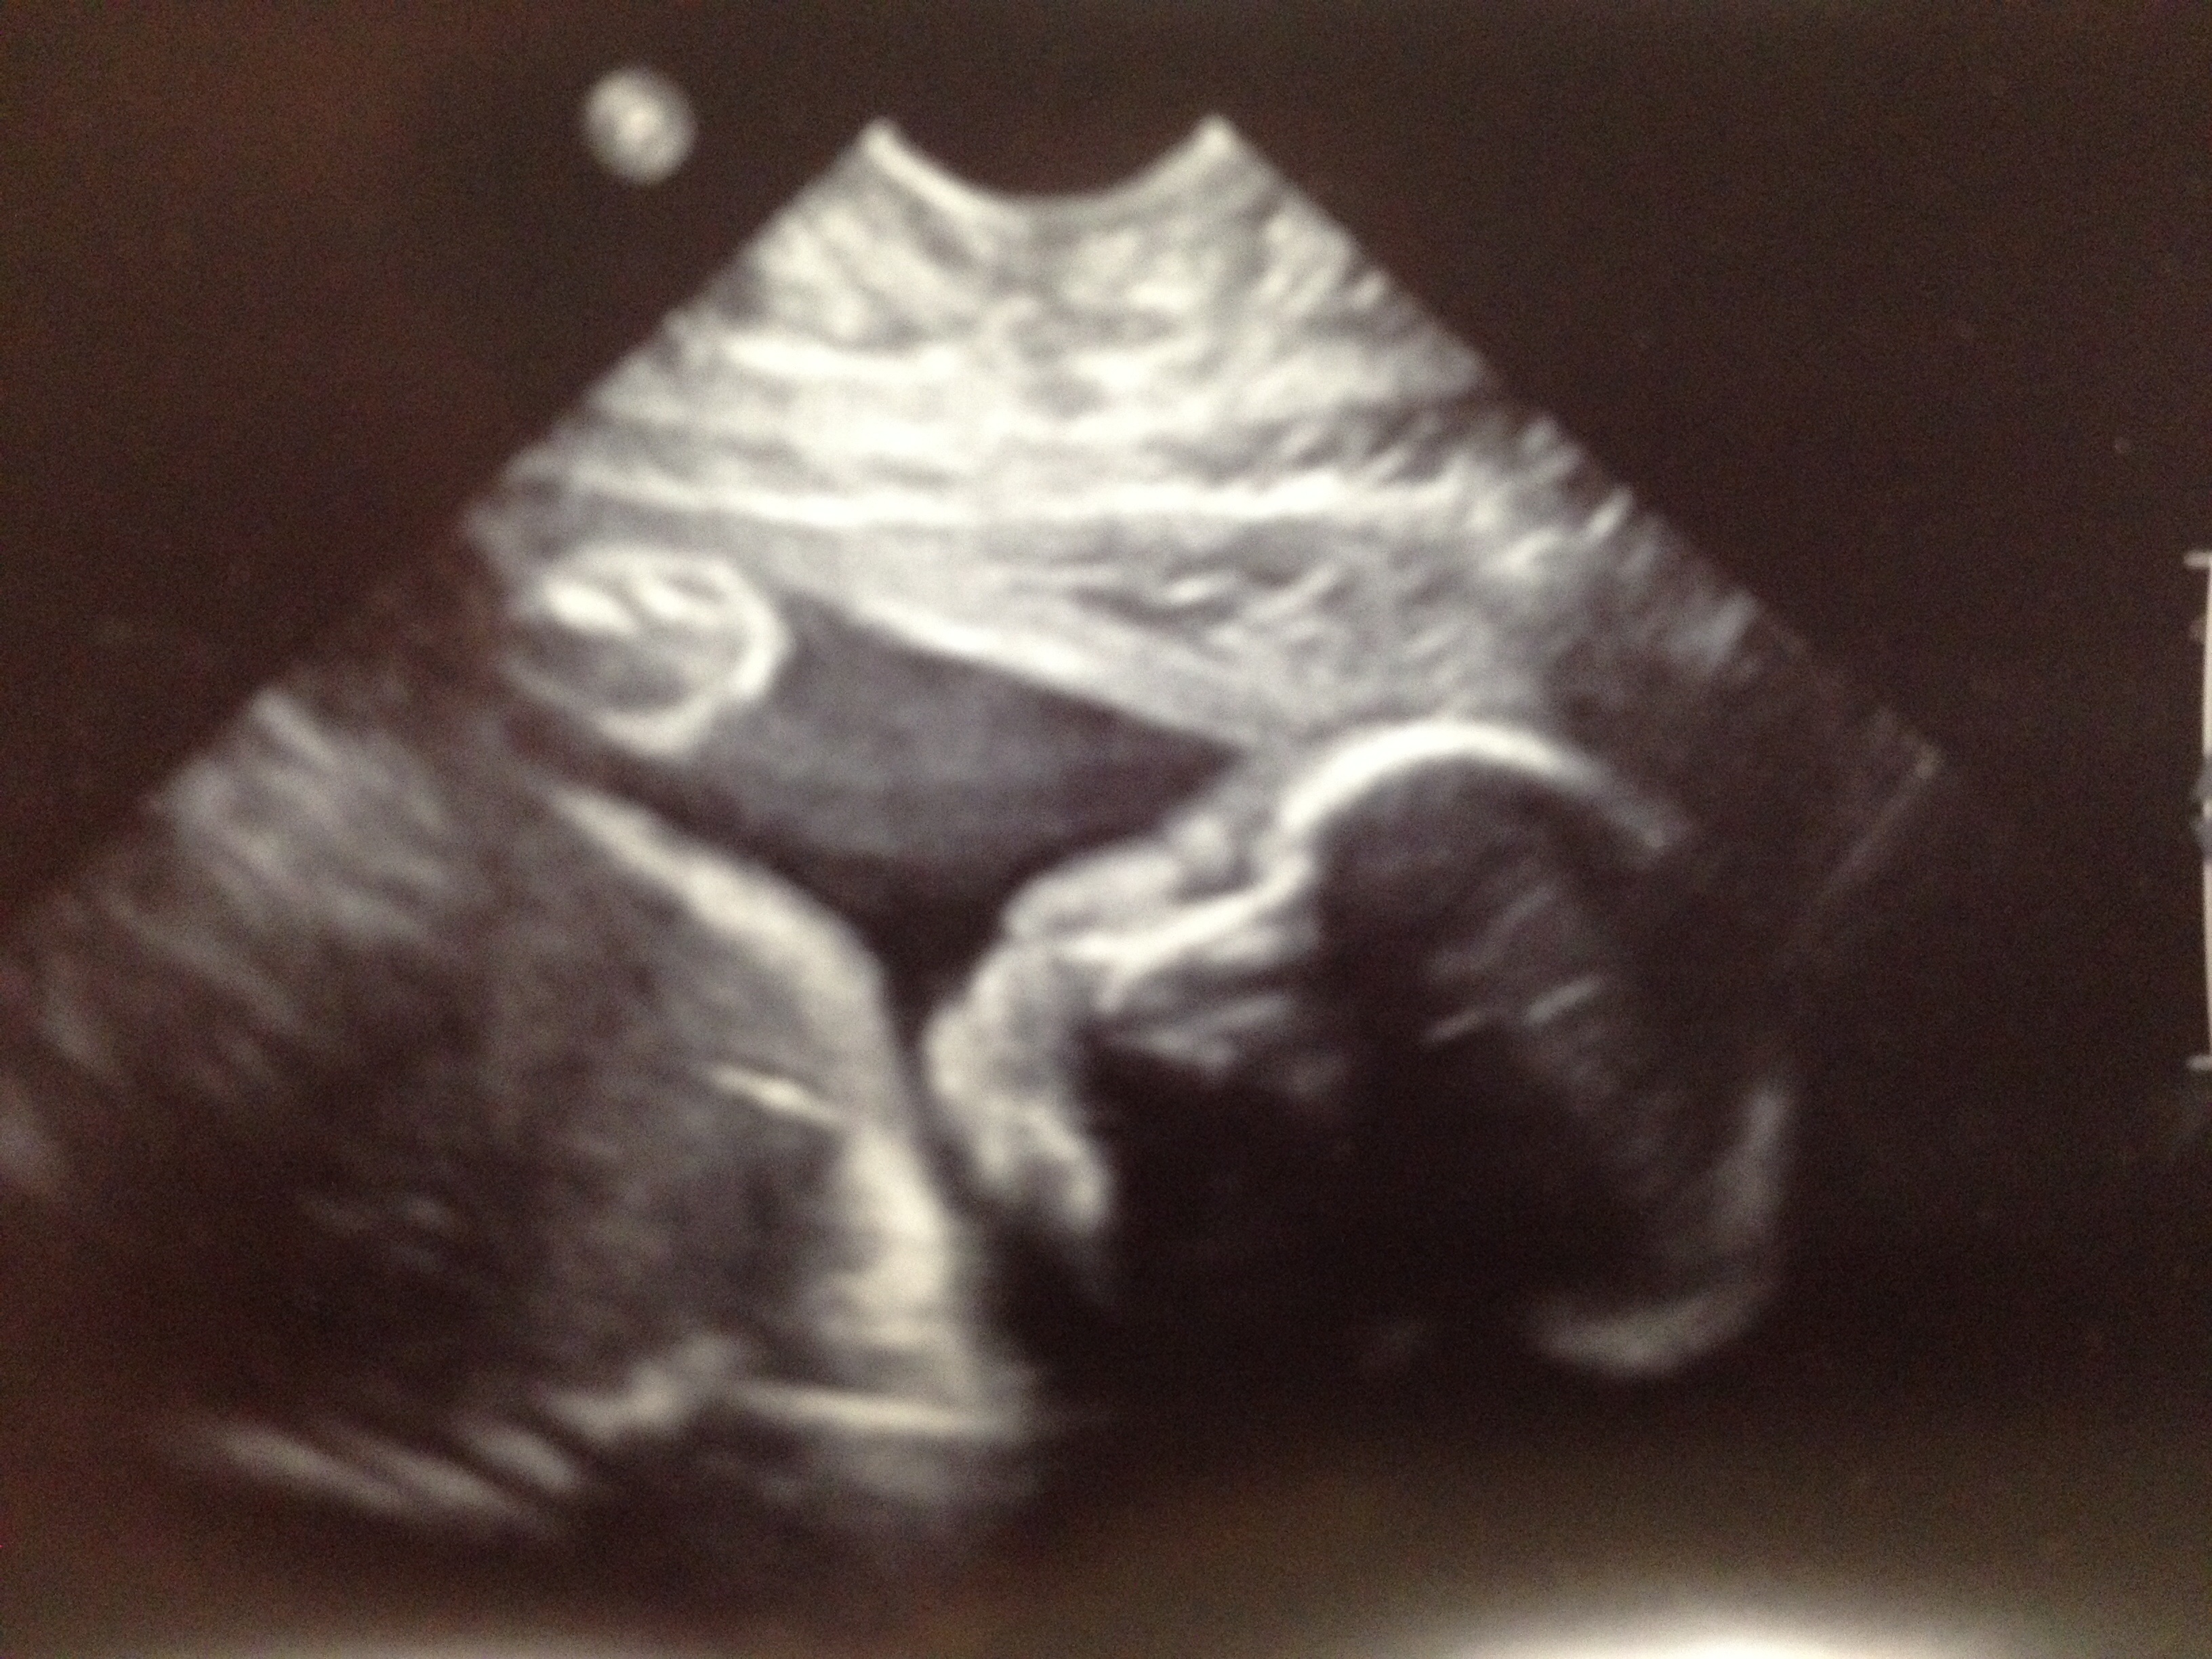

No 3d just a 2d from 26 w 3 day! I have a 3D/4D scheduled on the 28th. The 2d was great though. We got to watch little man suck on his big toe lol. He has DH's massive feet and my nose!

Feet and legs